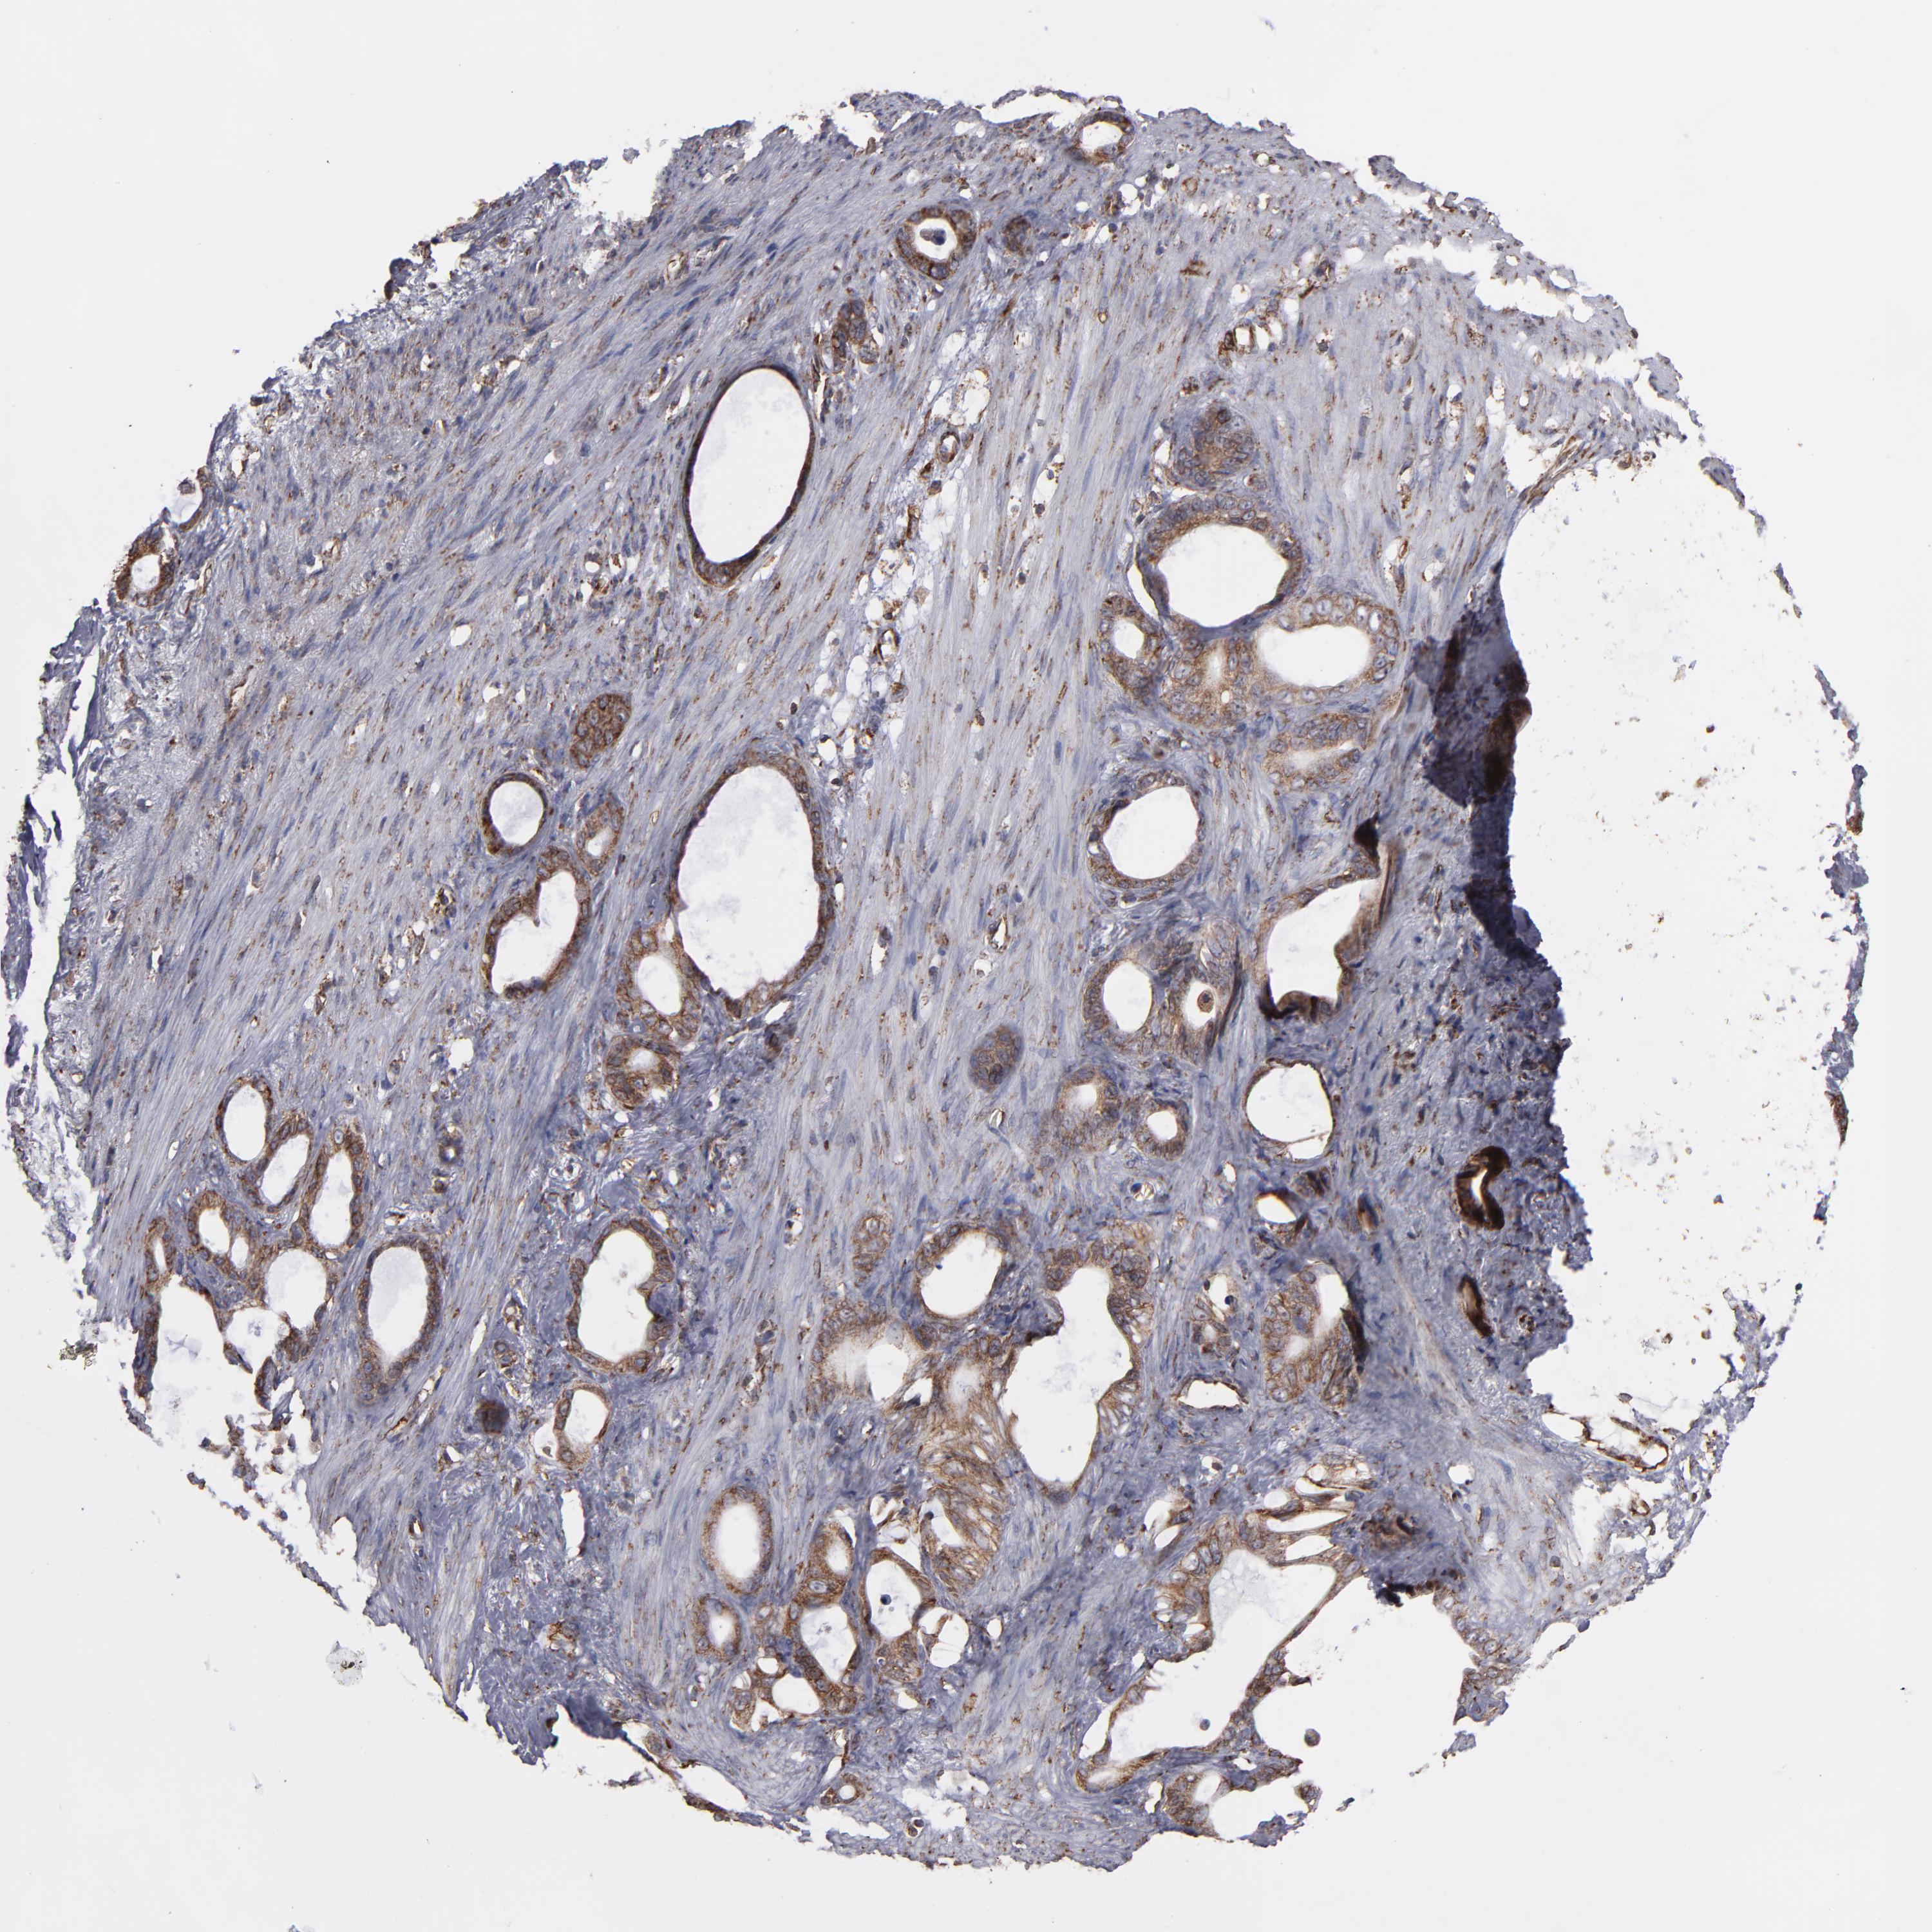

STOMACH CANCER - Protein expressioni

A mouse-over function shows sample information and annotation data. Click on an image to view it in a full screen mode. Samples can be filtered based on level of antibody staining by selecting one or several of the following categories: high, medium, low and not detected. The assay and annotation is described here.

Note that samples used for immunohistochemistry by the Human Protein Atlas do not correspond to samples in the TCGA dataset.

Antibody stainingi

Antibody staining in the annotated cell types in the current human tissue is reported as not detected, low, medium, or high, based on conventional immunohistochemistry profiling in selected tissues. This score is based on the combination of the staining intensity and fraction of stained cells.

Each image is clickable and will lead to virtual microscopy that enables deeper exploration of all samples and also displays staining intensity scores, fraction scores and subcellular localization as well as patient and tissue information for each sample.

Antibody HPA003178

Antibody HPA017876

Antibody CAB015331

Staining

High

Medium

Low

Not detected

Intensity

Strong

Moderate

Weak

Negative

Quantity

>75%

75%-25%

<25%

None

Location

Nuclear

Cytoplasmic/membranous

Cytoplasmic/membranous,nuclear

Adenocarcinoma, NOS

Adenocarcinoma, High grade